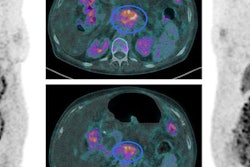

Lohrmann and colleagues investigated HuMab-5B1 with and without radiolabeling with zirconium-89 (Zr-89 DFO HuMab-5B1). Nine patients with metastatic malignancies that were positive for CA 19-9 received four whole-body PET/CT scans, the first performed on the first day of injection with the imaging agent, and then again on day 2 and around days 4 and 7. Individuals also had CT scans before the baseline PET/CT, which were used to verify the results of the radiotracer.

The researchers measured maximum standardized uptake values (SUVmax) for uptake of the agent in tumors. They found significant tracer uptake in local tumor recurrences, as well as in metastases. Uptake was analyzed for a total of 52 lesions; the highest uptake was seen on day 7 in the lymph nodes.

A 49-year-old woman with metastatic pancreatic adenocarcinoma presents with rising CA 19-9 levels. Axial fused PET/CT image with Zr-89 HuMab-5B1 shows focus of uptake in the liver (arrow), correlating with increased liver metastasis seen on diagnostic CT (red arrow) performed two weeks prior. Credit: Christian Lohrmann, Jason Lewis, Wolfgang Weber, Memorial Sloan Kettering Cancer Center; MabVax Therapeutics.PET/CT with Zr-89 DFO HuMab-5B1 led to the detection of very small tumors in the peritoneum and mesenteric lymph nodes that weren't found by CT alone, the researchers found. They concluded that the radiotracer could lead to improvements in the management of pancreatic cancer, including better tumor staging, improved surgical guidance, restaging of metastases, and potential drug selection for therapies that target CA 19-9.